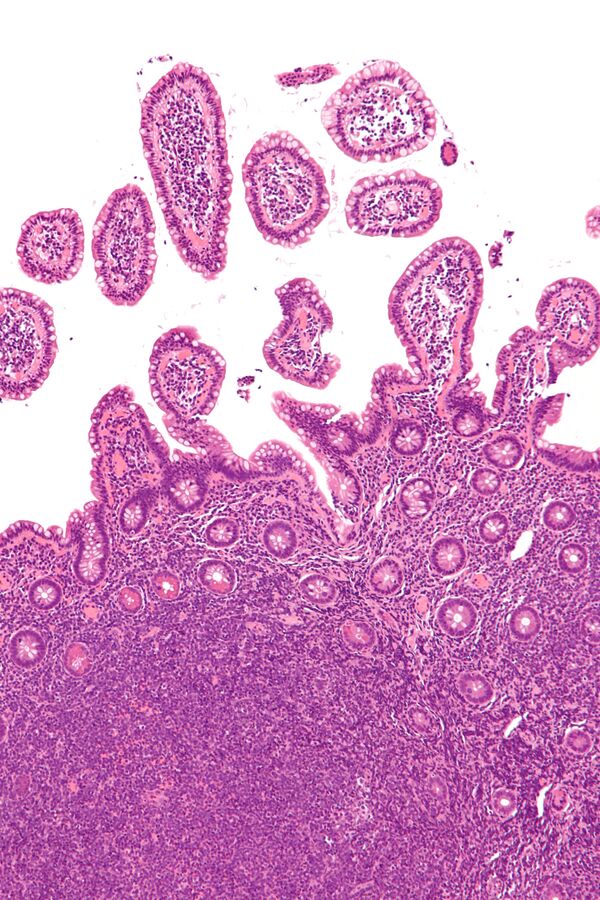

Отдельно в классификации выделяется лимфома Ходжкина, отличительной чертой которой являются клетки Берёзовского‑Штернберга‑Рид. В отличие от неходжкинских лимфом, она демонстрирует упорядоченное распространение поражения по лимфоузлам и отличается высокой излечиваемостью даже при распространённых стадиях. Один из наиболее частых гистологических подтипов — лимфома с нодулярным склерозом.